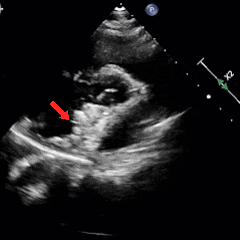

锁定后牵拉试验

锁定后,封堵器形态良好,超声下多切面进行牵拉试验,可见封堵器整体移动,右盘面未被拉开

释放前二次锁定

释放前进行二次锁定

主动脉短轴切面下,封堵器呈Y字型抱住主动脉根部,夹持稳定